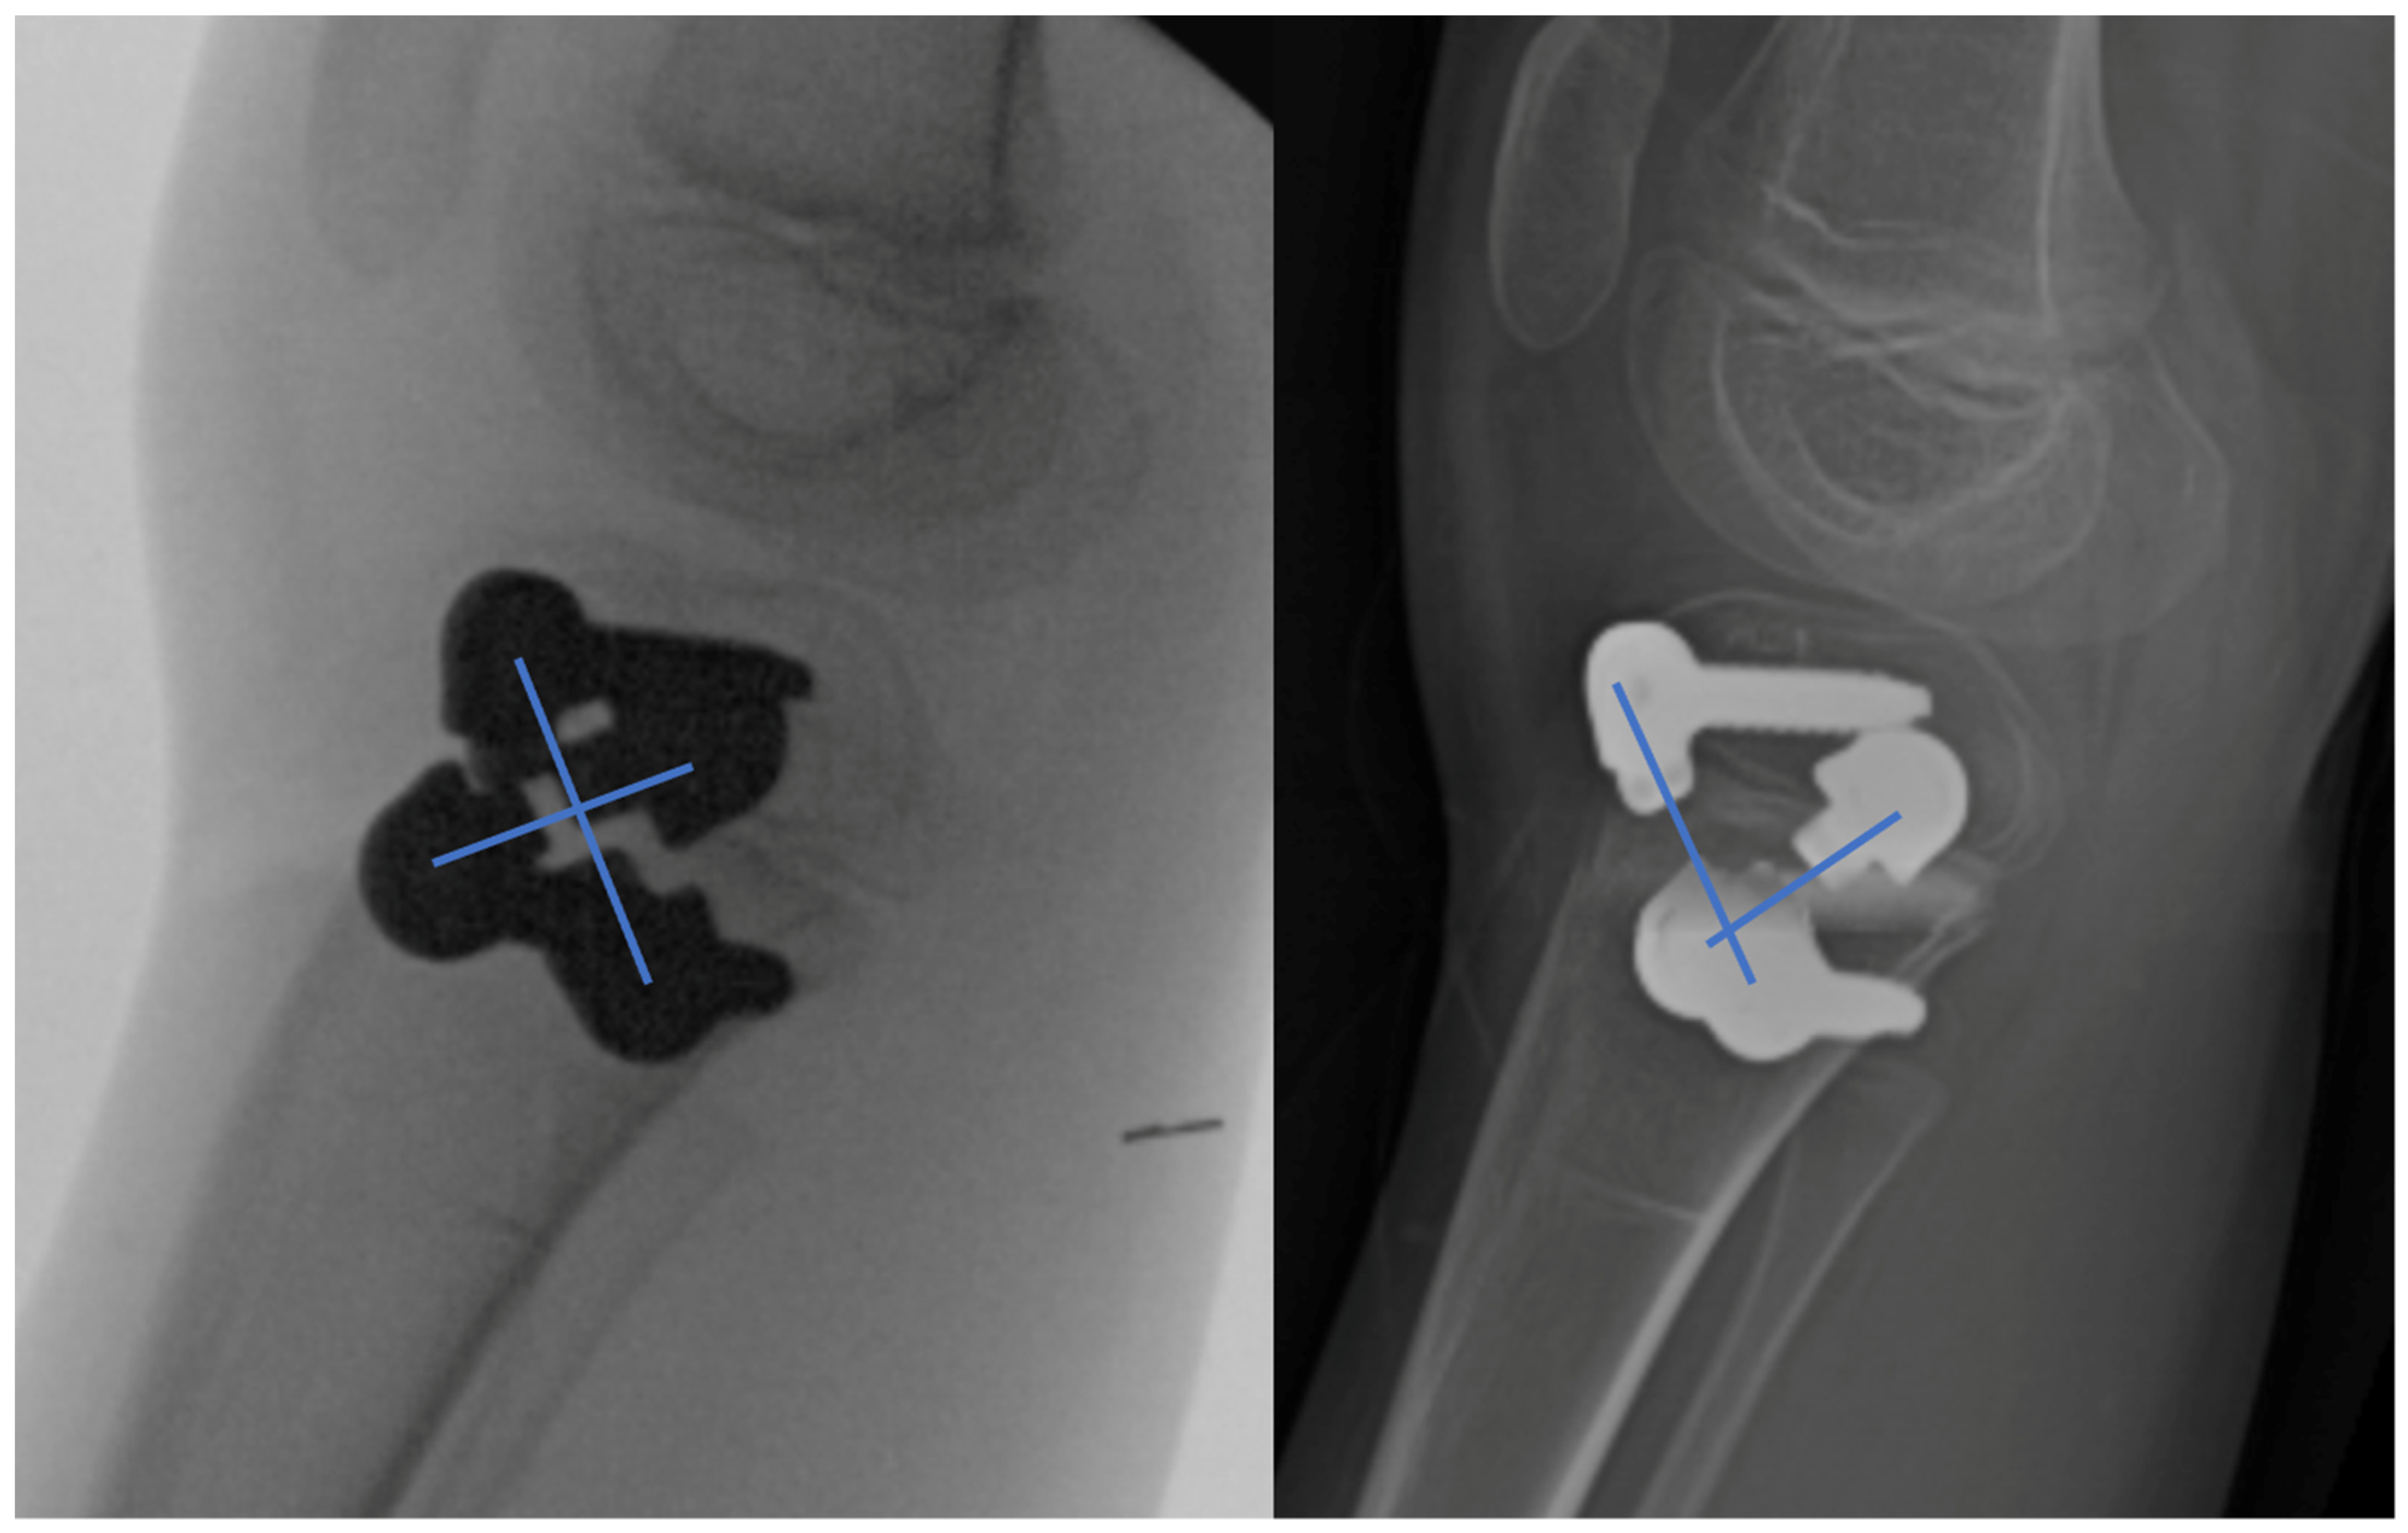

Rotational Guided Growth: A Preliminary Study of Its Use in Children

2. Materials and Methods

Surgical Technique

3. Results